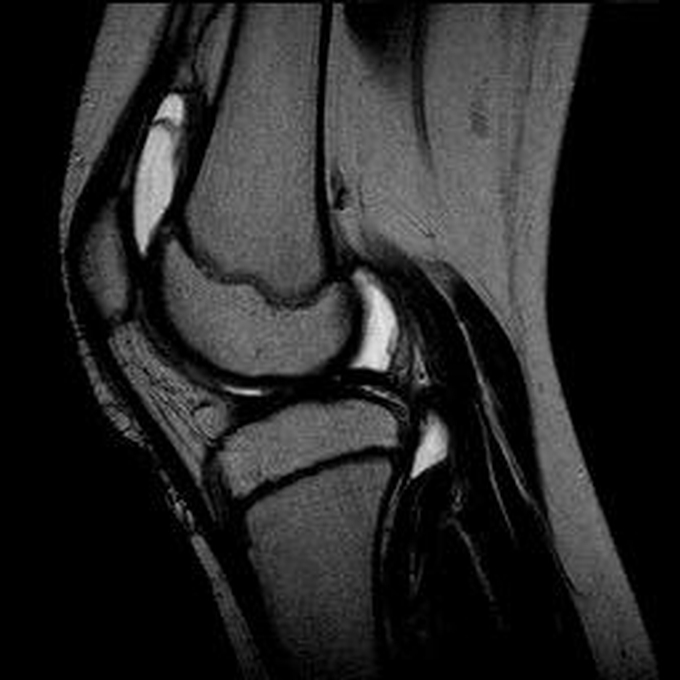

Haemophiliearthropathie bei Haemophilie A.

Arthropathia ARC123 Haemophiliearthropathie bei Haemophilie A.

MRT (high)